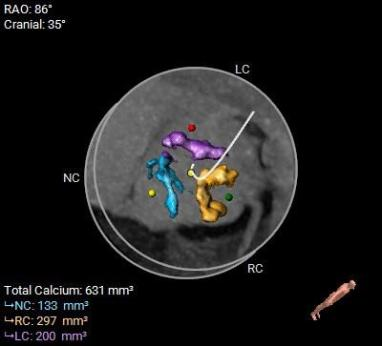

▲患者术前CT评估

该病例主动脉根部结构较小,并且左冠脉开口高度距离瓣环较近,只有10.2mm,有一定的冠脉阻挡风险,手术团队讨论后决定在TAVR时进行冠脉保护,提前将冠脉通路准备好,并且结合球囊扩张及瓣膜释放工作位综合评估。

综合以上分析及病例特点,手术策略如下:三叶式主动脉瓣,轻度钙化伴瓣叶增厚,左冠开口较低,右冠高度可,综合瓦氏窦内径、窦管交界内径等因素考虑,左冠行冠脉保护,非横位心,弓距弓角可,左室内径可,双侧入路血管走形良好,整体入路血管条件可。计划使用20mm球囊预扩,预装23型号瓣膜,释放高度零位开始释放,最终依据术中情况决定是否做烟囱支架冠脉保护技术。